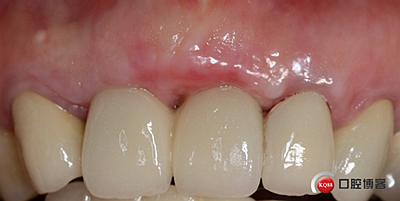

戴牙。

戴牙后半年復(fù)查。